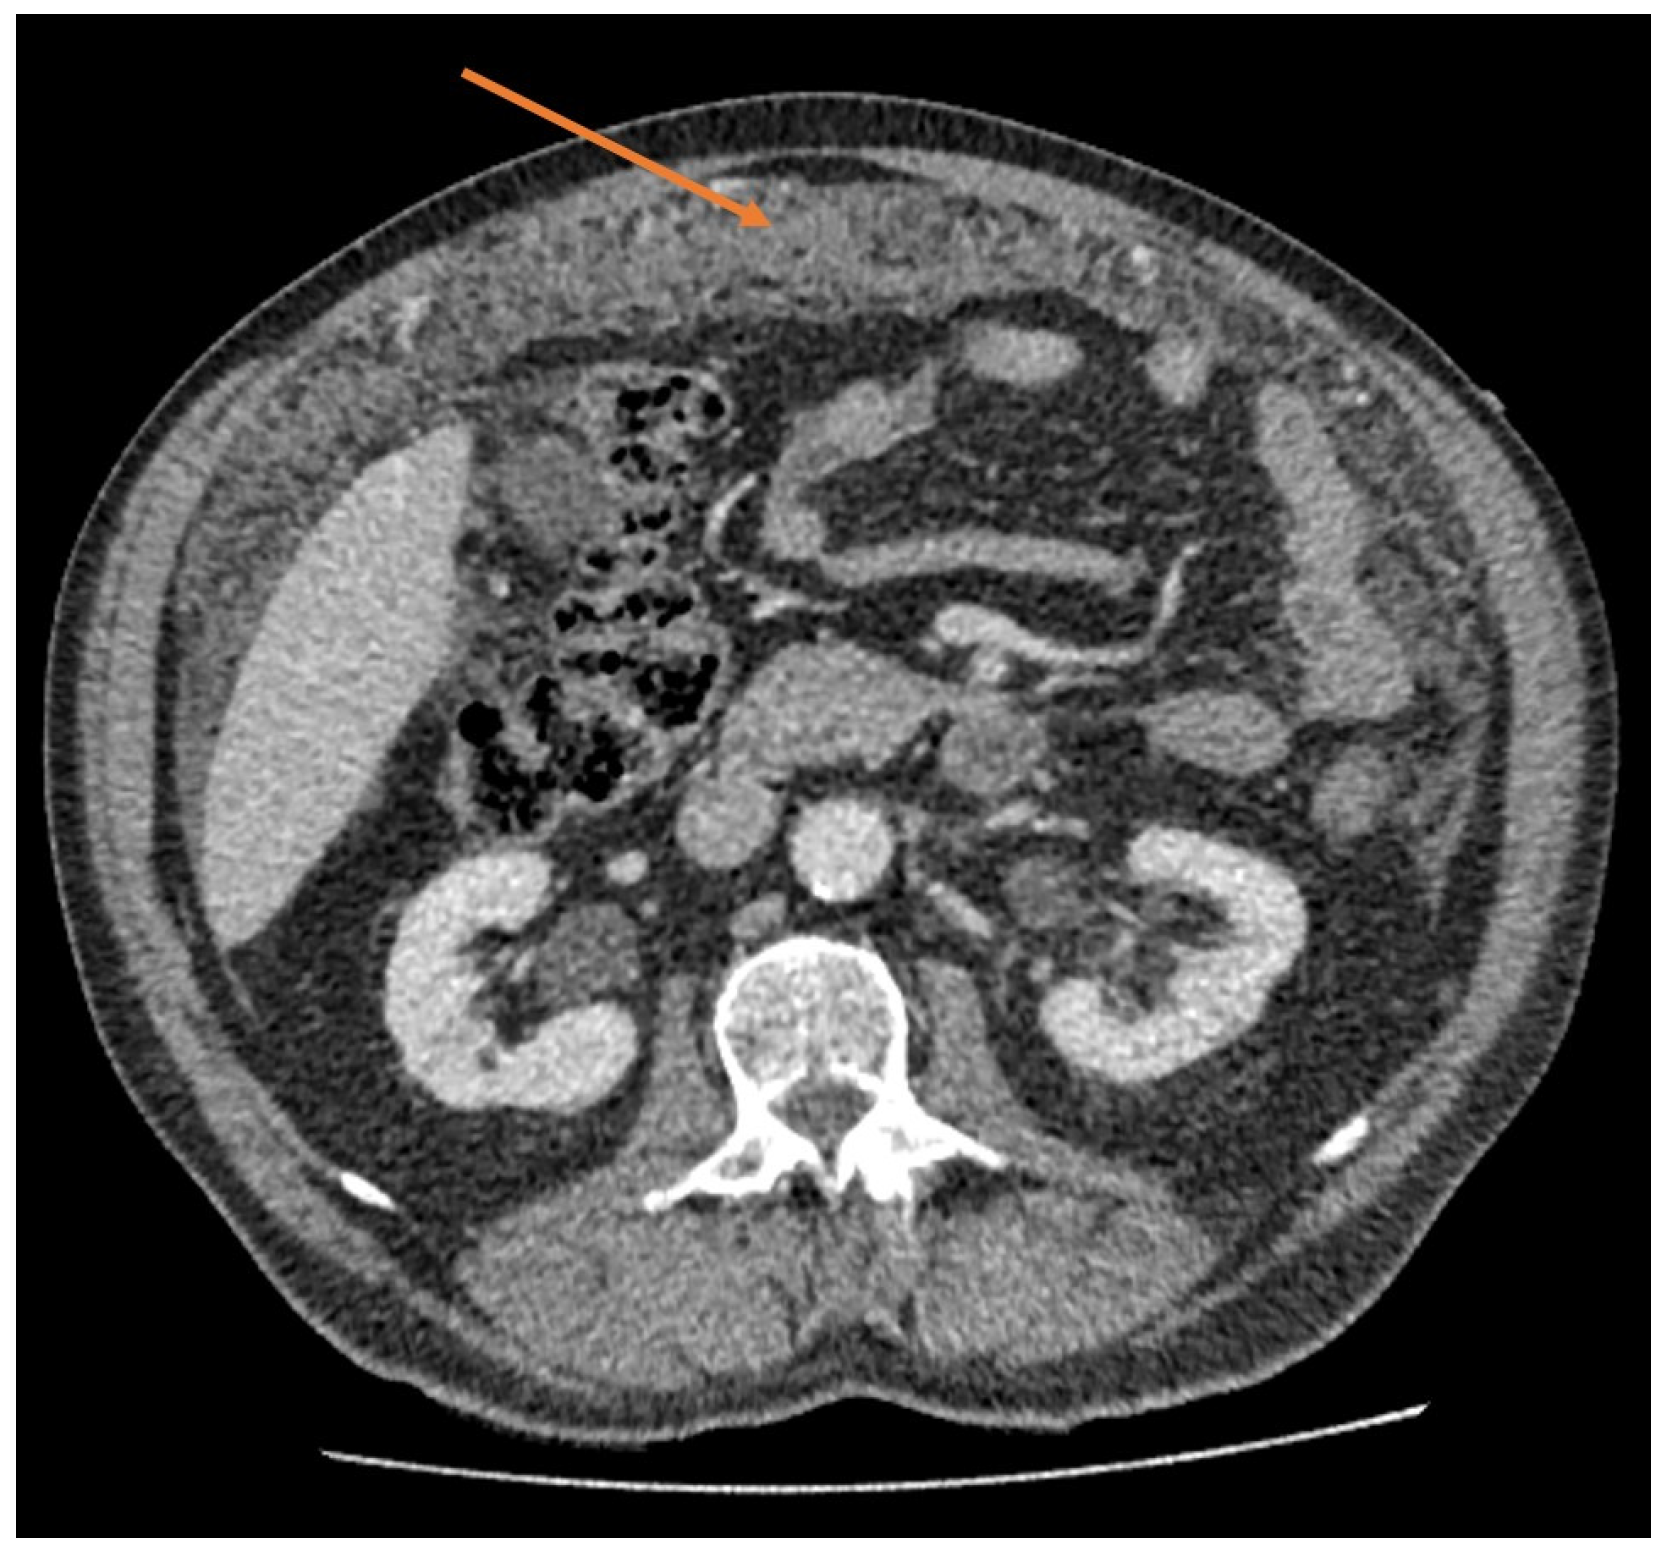

9. Imaging

- Park, J.Y.; Kim, K.W.; Kwon, H.J.; Park, M.S.; Kwon, G.Y.; Jun, S.Y.; Yu, E.S. Peritoneal mesotheliomas: Clinicopathologic features, CT findings, and differential diagnosis. AJR Am. J. Roentgenol. 2008, 191, 814–825. [Google Scholar] [CrossRef]

- Yan, T.D.; Haveric, N.; Carmignani, C.P.; Chang, D.; Sugarbaker, P.H. Abdominal computed tomography scans in the selection of patients with malignant peritoneal mesothelioma for comprehensive treatment with cytoreductive surgery and perioperative intraperitoneal chemotherapy. Cancer 2005, 103, 839–849. [Google Scholar] [CrossRef] [PubMed]